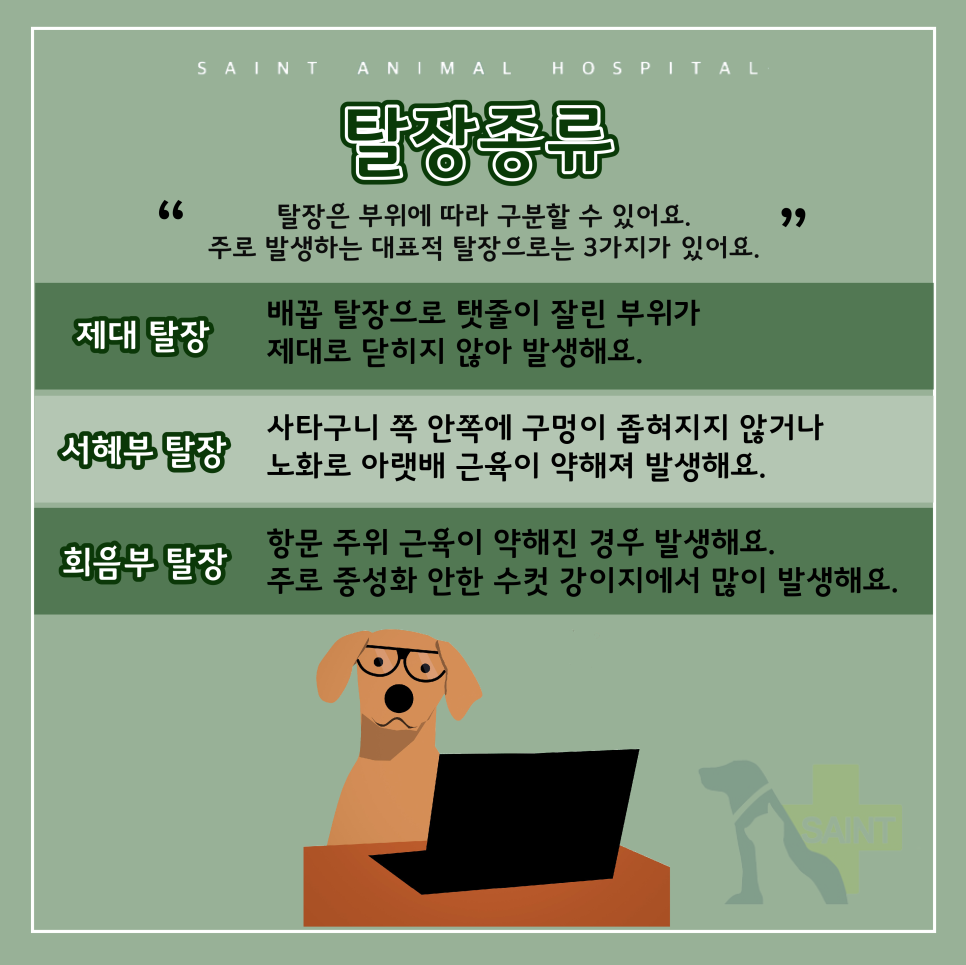

오늘 포스팅 할 내용은 강아지 탈장 교정 수술입니다.동물병원에 오는 개 중에 전역(배꼽) 탈장, 서해부 탈장, 회음부 탈장 등 생각보다 많은 개가 탈장하고 있습니다.

이러한 탈장의 원인은 대부분의 노화로 인한 근육조직의 결합력이 약해지기 때문입니다.

우리 몸은 여러 근육이 서로 교차하여 지지하고 있는데, 특히 항문 주위(회음부), 사타구니 주위(서혜부), 배꼽 주위(제대)에 분포하는 근육이 이완되면 복강 내의 복압에 의해 압력을 이기지 못하고 복강 내의 장기가 복강 밖으로 밀려나게 되어 이러한 현상을 탈장이라고 합니다.